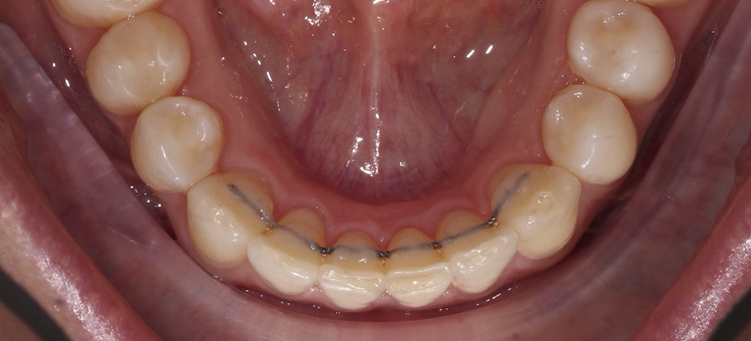

Исправление скученности фронтального отдела

Лечение скученности зубов элайнерами